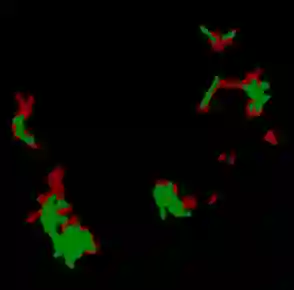

Until now, Coronavirus SARS-CoV-2 has caused more than 850,000 deaths and infected more than 27 million individuals in over 120 countries. Besides principal polymerase chain reaction (PCR) tests, automatically identifying positive samples based on computed tomography (CT) scans can present a promising option in the early diagnosis of COVID-19. Recently, there have been increasing efforts to utilize deep networks for COVID-19 diagnosis based on CT scans. While these approaches mostly focus on introducing novel architectures, transfer learning techniques, or construction large scale data, we propose a novel strategy to improve the performance of several baselines by leveraging multiple useful information sources relevant to doctors' judgments. Specifically, infected regions and heat maps extracted from learned networks are integrated with the global image via an attention mechanism during the learning process. This procedure not only makes our system more robust to noise but also guides the network focusing on local lesion areas. Extensive experiments illustrate the superior performance of our approach compared to recent baselines. Furthermore, our learned network guidance presents an explainable feature to doctors as we can understand the connection between input and output in a grey-box model.